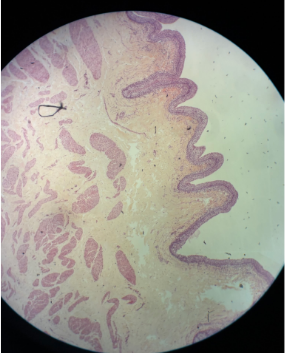

What is this a picture of?

Thick skin